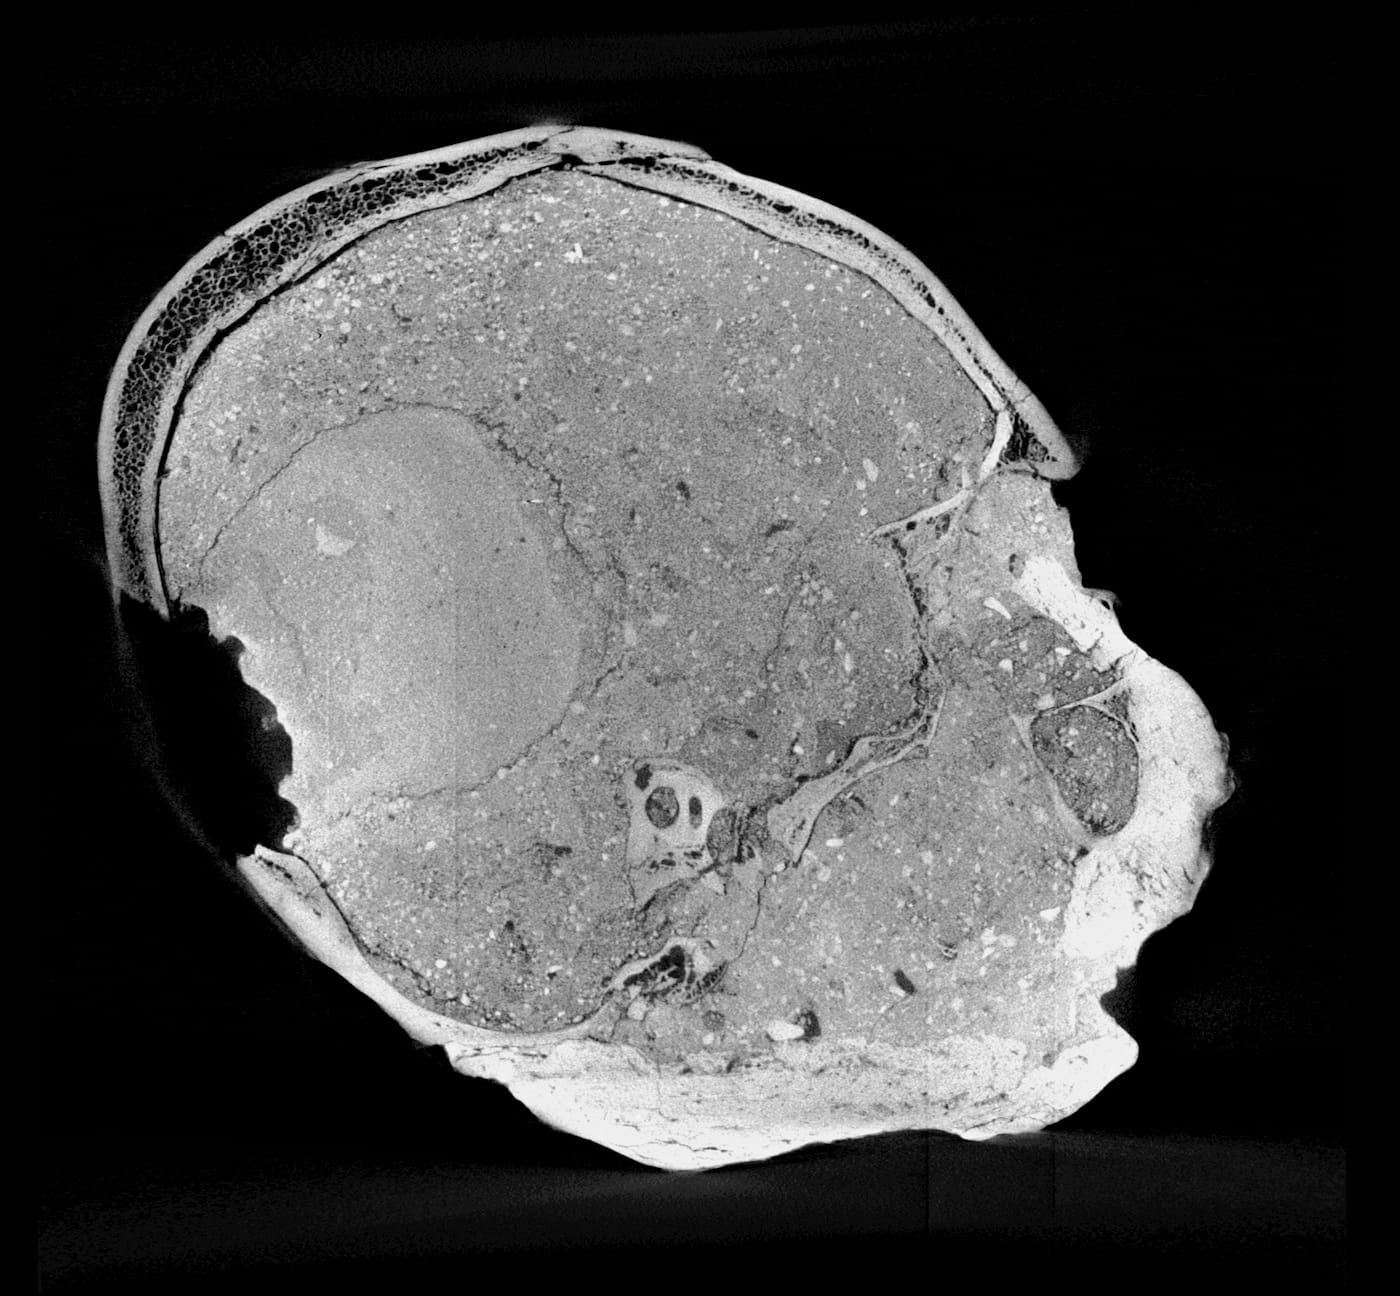

We now have an idea of what this particular individual looked like, as experts at the Natural History Museum’s Imaging and Analysis Center have used micro-CT scanning to create a 3D facial reconstruction of the Jericho Skull. The head, which is currently on display, depicts a man in at least his 40s who likely underwent ritual skull reshaping when he was younger, as suggested by the slight broadening of his head across the back.

The imaging team conducted its own sculptural process, but one, of course, aided with the latest digital technologies. Experts first digitally separated the shape of the skull bones from the overlying plaster then converted data from a micro-CT scan to create a 3D-printed model of the cranium. As the mandible was not present, the team added a lower jaw constructed based on data from other known examples of human mandibles of similar age and geographic origin. The face was then built over the skull model — this time, in a more traditional sculptural process: experts used clay and wax to build features from the bone-up, muscle by muscle, creating every anatomical detail before topping it off with a clay layer of tissue and skin. Finally, they made a mold of the head from which the displayed face was cast in Jesmonite — essentially a mixture of gypsum and acrylic resin.